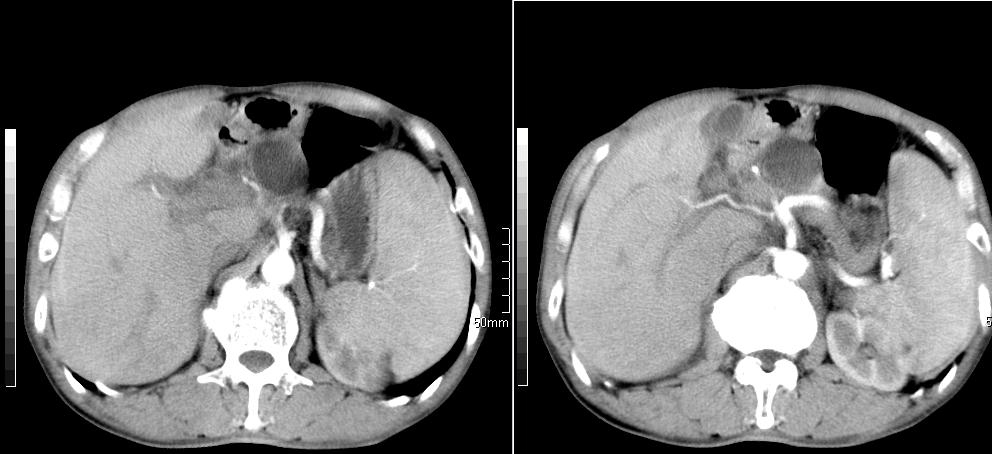

标题: CT26769:男,58岁,腹胀、腹部不适一年余 [打印本页]

标题: CT26769:男,58岁,腹胀、腹部不适一年余

肝右叶后段见小片状略低密度影,边缘不清,轻度强化,内见小血管影通过同,延迟期为等密度,考虑局灶性脂肪浸润。需与血管瘤鉴别。另有胆囊炎、脾大。

肠系膜脂膜炎,胆囊炎,脾大。建议结合临床。鉴别:慢性胰腺炎并假囊肿形成。

1 慢性胰腺炎并假囊肿形成。2 慢性胆囊炎并累及肝边缘!

1)考虑慢性胰腺炎并假性囊肿形成。2) 慢性胆囊炎。3)肝内胆管扩张。

1肝内胆管扩张,性质待定,2慢性胰腺炎胰管扩张,胰腺颈部假囊肿,3肝左叶低密度为小囊肿,4胆囊炎。